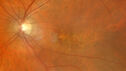

Recurrent toxoplasmosis with elevated IOP33 views48 year old man with 4 episodes over 40 years of vision loss from toxoplasmosis. His IOP was 44 on presentation.

Recurrent toxoplasmosis with elevated IOP30 views48 year old man with 4 episodes over 40 years of vision loss from toxoplasmosis. His IOP was 44 on presentation.

Recurrent toxoplasmosis with elevated IOP27 views48 year old man with 4 episodes over 40 years of vision loss from toxoplasmosis. His IOP was 44 on presentation.

Recurrent toxoplasmosis with elevated IOP26 views48 year old man with 4 episodes over 40 years of vision loss from toxoplasmosis. His IOP was 44 on presentation.